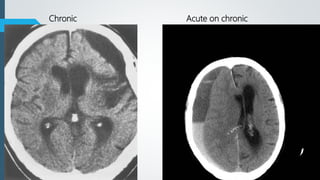

Age of SDH

 Chronic – 3 weeks to months

CT Findings

 60% homogenously hyperdense

 40% mixed hyper-, hypodense with active bleeding (Swirl sign)

 Subacute

 Iso to hypodense

 GM-WM junction displaced medially

 Progression from hyper to iso to hypodense over nearly 3 weeks.

 Recurrent hemorrhage results in mixed density.

 Chronic

 Typically follows CSF density

 Calcification can be seen along periphery of chronic collections, typically those

present for many years

** If no new hemorrhage, density decreases by +- 1.5 HU

Acute SubacuteAcute

Chronic Acute on chronic